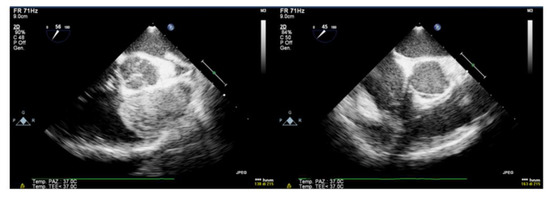

Contrast CT scan confirmed the presence of a heterogeneously enhancing soft-tissue mass occupying the RVOT with no evidence of pulmonary embolization (Figure 4).

Post-contrast CT confirms the presence of an ovoidal mass with smooth margins anchored to the infundibular septum posteriorly, determining significant RVOT obliteration as shown in this frontal and later multiplanar reformatting view. The lesion has small tissue density with mild enhancement and patchy distribution. There was no CT evidence of mass infiltration, pericardial effusion or pulmonary embolism.